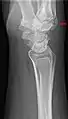

Carpal boss in plain X-Ray.

The joint between the index metacarpal and the capitate is a fibrous non-mobile joint. Some people have a gene that leads to this growth. It looks like arthritis (bone spurs on each side of the joint) on X-ray. It looks like a ganglion on the hand, but more towards the fingertips.